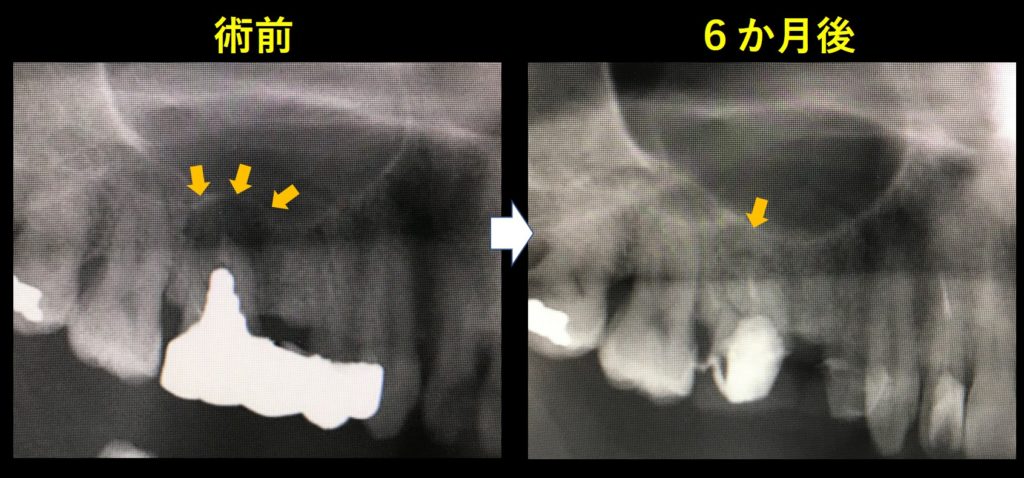

レントゲン写真です。

左が術前、歯茎の腫れおよび動揺が確認されました。矢印部分に黒い影が見られます。根の先の骨が感染で溶けています。

右が根管治療後です。歯茎の腫れ、動揺も改善し、レントゲン上で矢印部分の骨の再生が確認できます。